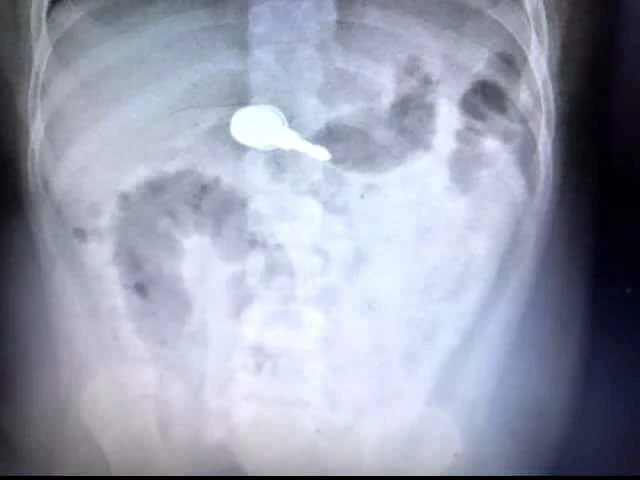

Hình ảnh chùm chìa khóa nằm trong dạ dày bé trai. Ảnh: BVCC

Tuy nhiên, sau hai ngày chờ đợi, chùm chìa khóa không được thải ra ngoài nên gia đình đưa bé vào BV Nhi đồng TP. Tại đây, các bác sĩ đã nội soi kéo ngược được chùm chìa khóa qua miệng mà không làm trầy xước các cơ quan bên trong cơ thể. Chùm chìa khóa sau hai ngày ở trong dạ dày bé trai đã rỉ sét.